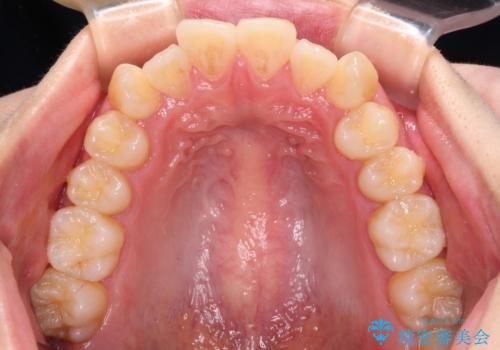

上下ともに歯列が前方に突出していたため、上下左右の第一小臼歯4本を抜去し、ワイヤー装置による矯正治療を行うこととしました。

舌の突出癖による影響もあったため、舌のトレーニングを並行して実施しました。

上下左右4本抜歯する場合には、通常2年から2年半ほどの期間を要しますが、舌のトレーニングをしっかりと行っていただいたことで、1年9ヶ月で終了することができました。